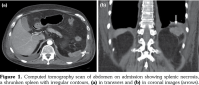

In clinical admission, his physical examination showed no evidence of systemic infection with a body temperature of 37.2°C. Laboratory findings at his first admission were summarized in Table 1. Computed tomography (CT) scan revealed a cavitary lesion of 6 mm in diameter located in the left upper lobe (which was also seen in his previous chest CT) besides a shrunken spleen as a recent finding (Figure 1).

To date, splenic involvement has been reported rarely in GPA; in fact, it is thought to be underestimated as it is often asymptomatic.[1,12] Spleen pathologies that can be seen in GPA include splenomegaly, capsular adhesion, splenic artery-vein thrombosis, granuloma formation, splenic infarct and hemorrhage, rupture or abscess as a complication of splenic infarct.[1,12] In GPA, splenic infarct occurs as a result of occlusion of the distal part of splenic artery and its branches.[13] In our patient, splenic findings seen in the CT scan possibly improved as a consequence of previous splenic infarctions. Although Doppler ultrasonography of the splenic artery and vein could not be performed, septic embolism was ruled out by echocardiography. Splenic infarct and rupture have also been reported during acute CMV infection.[14] However, in our case, a shrunken spleen, rather than a recent infarct, was detected during CMV colitis, which suggested that spleen involvement could be primarily related to GPA.